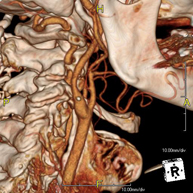

Prova radiològica que consisteix en obtenir imatges de l'os penyal del temporal (oïda interna, mitjana i externa) d'alta definició anatòmica, mitjançant l'ús d'un equip de TC (Tomografia Computeritzada). Indicacions: pèrdua d'audició sobtada o crònica, quadres vertiginosos, mareig, malformacions congènites. - Angio-TC Troncs Supraaòrtics

Prova radiològica que consisteix en obtenir imatges de les artèries caròtides del coll d'alta definició anatòmica, mitjançant l'ús d'un equip de TC (Tomografia Computeritzada) i la injecció de contrast intravenós. Posteriorment, les imatges són reconstruïdes en tres dimensions (3D). Indicacions: accident vascular cerebral agut, accident vascular transitori, buf cardíac. - TC Columna cervical